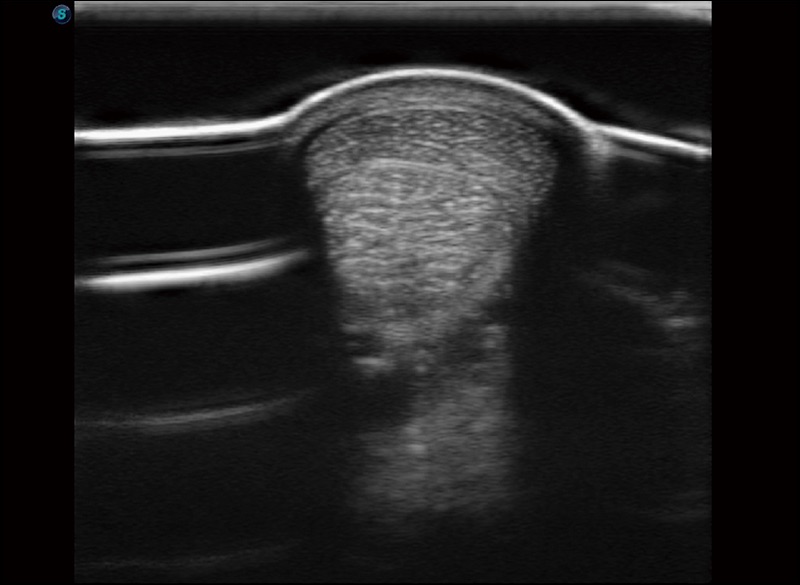

α1卓越的图像质量和便捷的工作流程,使每位宠物医生都能轻松扫查。其全面的兽用应用功能和紧凑型的结构设计,可以满足动物检查的多种需要。专业的预设检查模式和多领域测量软件包有助于为不同类型的动物提供检查, 让宠物医生能够出色的完成工作。

扩展成像

支持线阵和凸阵探头,一键操作即可获得更宽的图像视野

穿刺针增强

高清显示穿刺进针情况